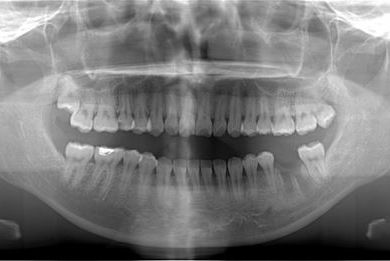

| 性別/年齢 | 女性 / 27歳 | ||||||||||||||||||||||||||||||||

| 主訴 | キャンペーンインプラントを受けたい。 | ||||||||||||||||||||||||||||||||

| 治療方針 | インプラント治療にて、機能的・審美的回復を行う。 | ||||||||||||||||||||||||||||||||

| 治療内容 | インプラント1本、メタルボンドセラミッククラウン1本 | ||||||||||||||||||||||||||||||||

| 総治療費 | 252,000円 | ||||||||||||||||||||||||||||||||

| 治療期間 | 4ヶ月 |